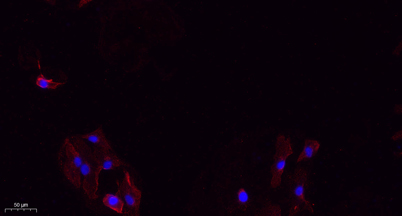

IF

Recomended Dilution Western Blot: 1/500 - 1/2000. IHC-p: 1:100-300 ELISA: 1/20000. IF 1:100-300 Not yet tested in other applications.